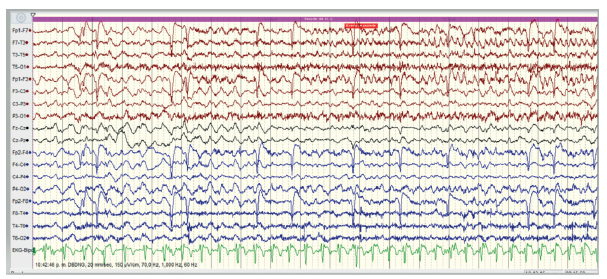

En más del 90 % de los pacientes con ELTm se identifican puntas y ondas agudas con máximo voltaje en la región temporal anterior, aisladas o en pequeños grupos, con mayor frecuencia durante el sueño N1-N2 (figura 1) 20. Las descargas epileptiformes medio-temporales se asocian con un generador temporal más grande o extramesial. Aproximadamente un tercio de los pacientes tienen descargas epileptiformes interictales (DEI) temporales bilaterales, que se hacen evidentes con la monitorización EEG a largo plazo 21. En la ELTm las ondas lentas tienen un valor localizador. La actividad delta rítmica intermitente temporal se observa en una minoría de pacientes, pero se asocia con ELT hasta en un 80 % 22.

Figura 1 Inicio de crisis epiléptica en región temporal anterior izquierda (electrodos F7-T3-T5) con actividad delta inicial, seguida de actividad theta 7, segundos después

La actividad theta o alfa regular rítmica, temporal anterior, focal unilateral (típicamente 5-9 Hz), asociada con una semiología concordante, es una característica distintiva de la ELTm figura 1). Este patrón eléctrico ocurre en más del 94 % de los pacientes y lateraliza de forma correcta la zona de inicio ictal en el 95 % de los casos. En la ELTm el inicio eléctrico de las crisis focales se presenta generalmente unos 30 segundos antes del inicio clínico. En los registros de EEG invasivo se comprueba que cuando el ritmo ictal compromete solo al hipocampo no se detectan alteraciones en el EEG de superficie hasta que se recluta la neocorteza temporal inferolateral. Cuando la descarga ictal se restringe a la corteza temporal mediobasal, se registra un ritmo dominante en el vertex, asociado con una orientación vertical del dipolo con registro en las regiones centrales. Los mejores resultados quirúrgicos se obtienen cuando en el EEG se combinan las DEI temporales unilaterales (100 %) y permanecen regionalizadas sin propagación contralateral. El enlentecimiento regional postictal puede aparecer en más del 70 % de los pacientes con ELT y puede ser útil como signo localizador.